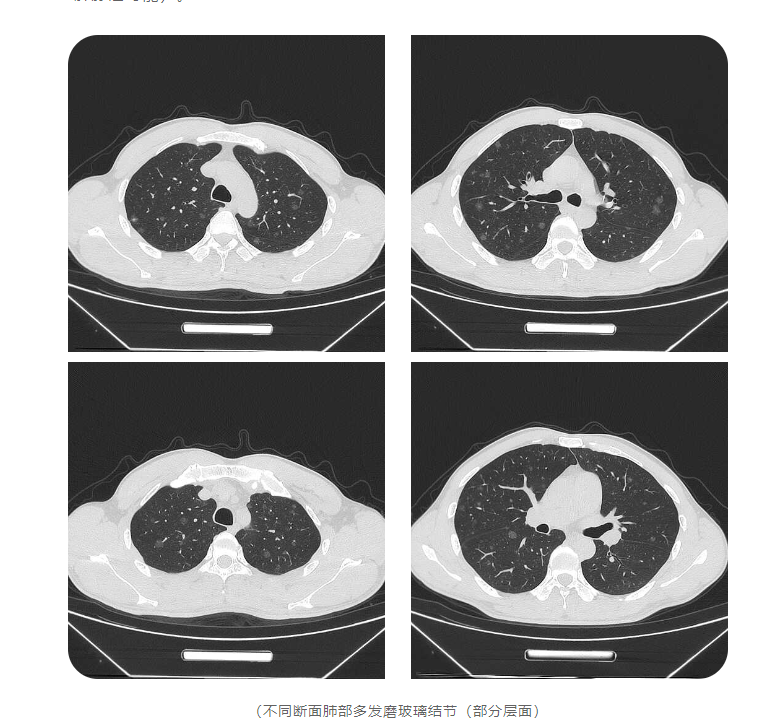

d2.png

“我发起了肺结节多学科联合会诊,胸外科、呼吸与危重科、影像科的专家都来了。”姚克林说,通过激烈讨论、反复论证,大家最终提出了适合胡军的个性化治疗方案:在放射介入科完成选定的高危靶结节穿刺定位,然后在胸外科行腔镜下结节微创切除活检,获取病理结果和肿瘤基因检测结果。结果显示,胡军患有肺腺癌。